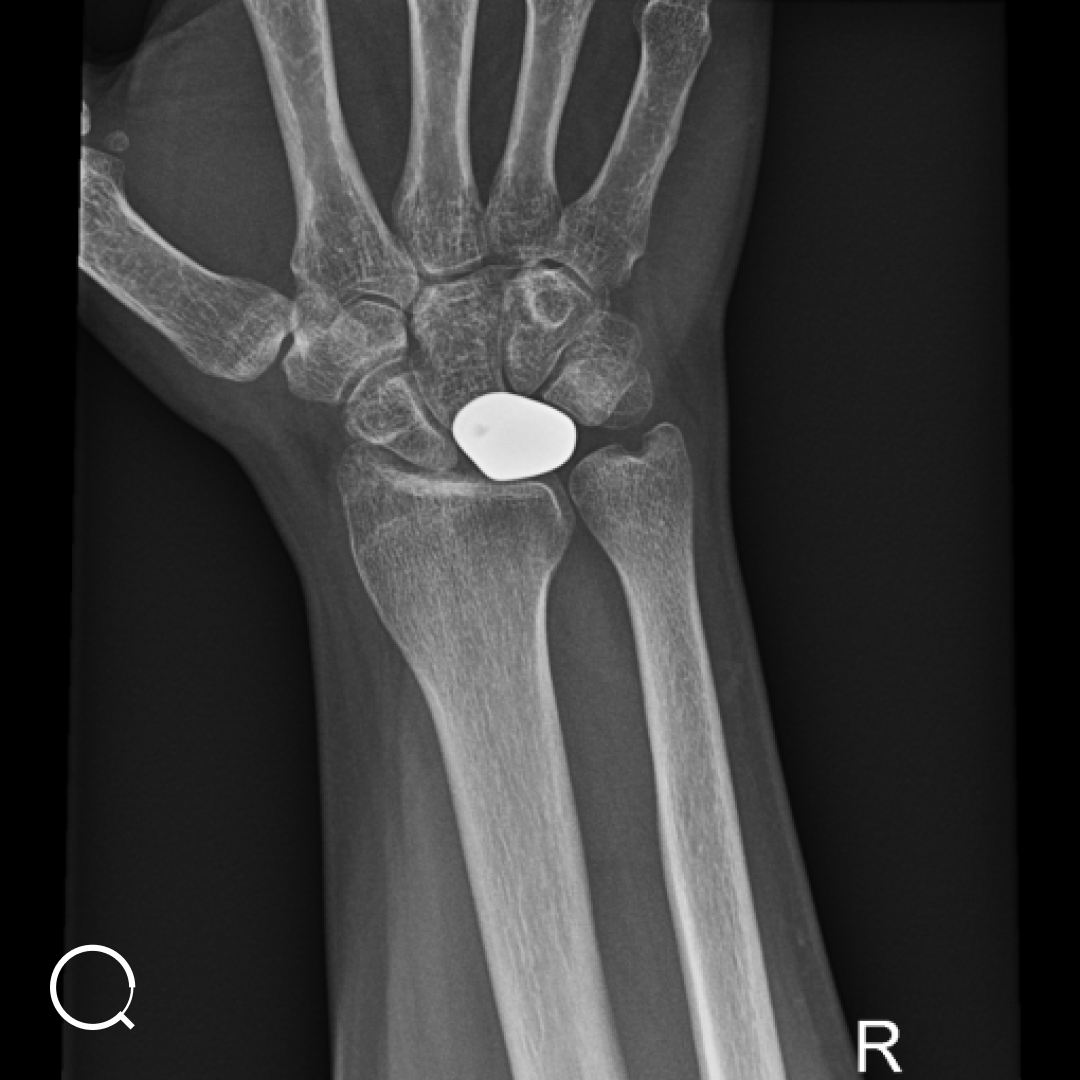

Prof. Vanhees: “Gevorgyan kampte met avasculaire necrose van een bot (os lunatum) in zijn hand, een aandoening waarbij een bot afsterft door een gebrek aan bloedtoevoer. Dit veroorzaakte hevige pijn en dreigde zijn mobiliteit volledig te beperken.

Traditionele behandelingen, zoals een polsfusie, zouden de pijn kunnen verlichten, maar zouden ook de beweeglijkheid van zijn pols beperken. Voor een jonge, actieve man zoals Gevorgyan was dat geen ideale oplossing.”

Prof. Vanhees: “We hebben gekozen voor een 3D-geprinte prothese, volledig op maat gemaakt voor Gevorgyan. Een 3D-scan van zijn gezonde hand leverde de basis om een zo nauwkeurig mogelijke replica te maken van het beschadigde botje.

Dankzij onze samenwerking met CADskills konden we de prothese printen in titanium, een sterk en bio-compatibel materiaal dat uitstekend door het lichaam wordt geaccepteerd.”

Prof. Vanhees: “Tijdens de operatie hebben we de beschadigde botje vervangen door de prothese. Dankzij de precisie van de 3D technologie paste de prothese perfect. Gevorgyan voelde direct verlichting van de pijn en kon snel beginnen met revalidatie oefeningen.”